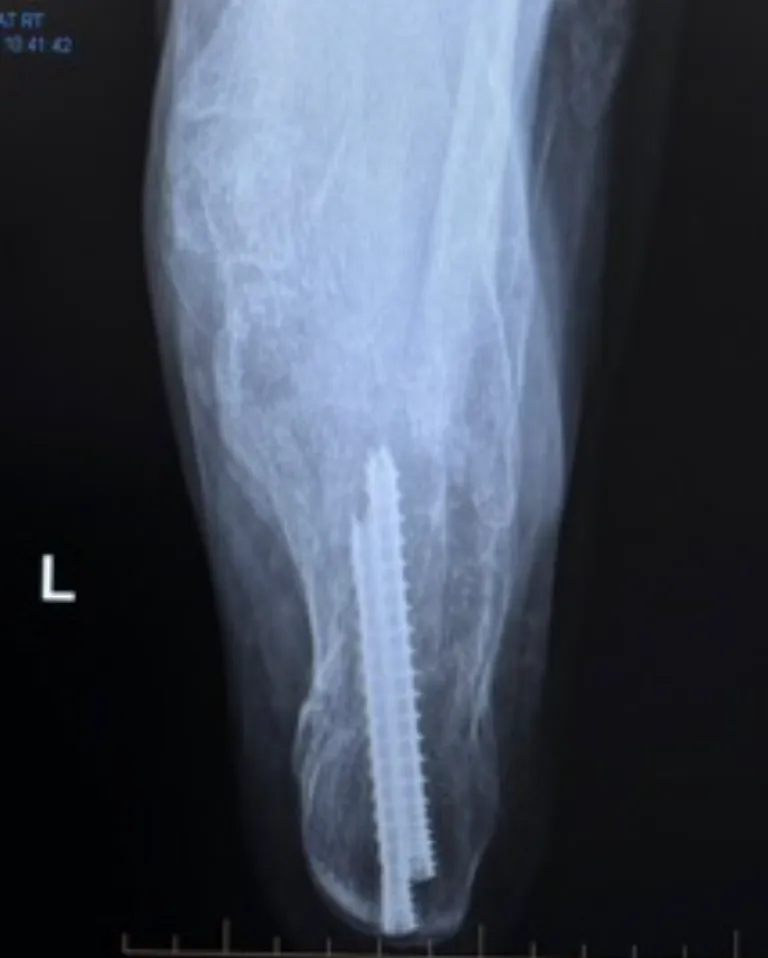

Standard X-rays of this bone can be hard to interpret and may miss the fracture or under-represent the extent of the injury.

- Open fixation

- Arthroscopic fixation

- Percutaneous (minimally invasive) fixation

- Primary subtalar fusion for severely comminuted patterns

Extended lateral (L-shaped) incision:

Large incision on the outside of the heel. Provides excellent exposure but carries a higher risk of wound complications. Uses a specific and large plate to secure the fragments.

Sinus tarsi incision:

Smaller incision on the outside of the heel. Provides a more limited exposure but significantly reduced soft-tissue risks, and therefore commonly preferred. Fixation is with a specific sinus tarsi plate.